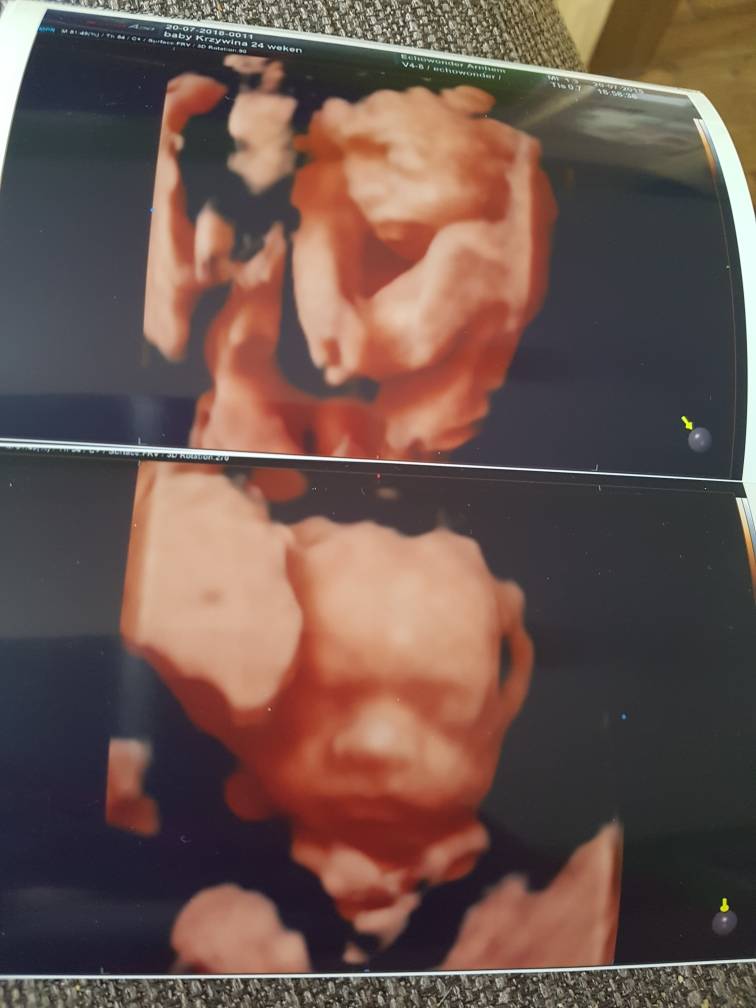

Weronika, śliczna Calineczka